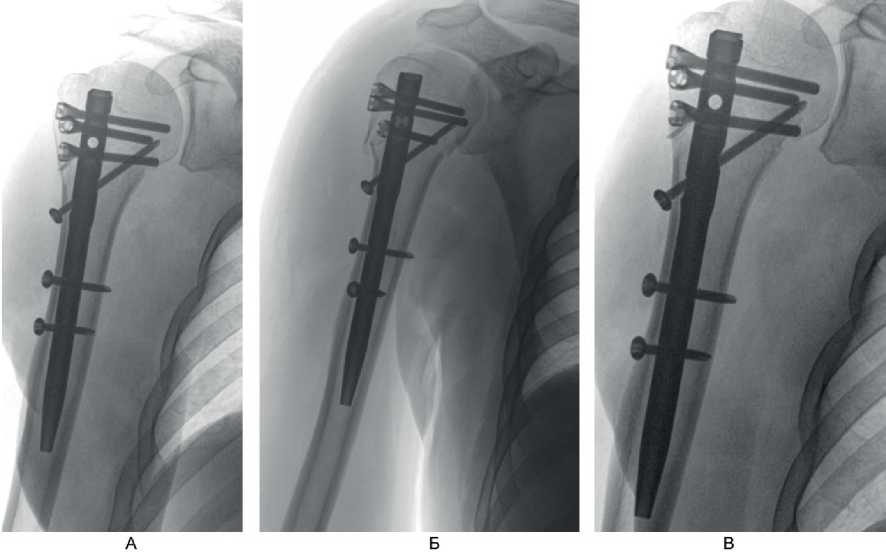

На контрольном осмотре через 6 мес у 7 (63,6 %) пациентов этой группы отмечено полное восстановление функции в плечевом суставе, у 4 (36,4 %) больных – небольшое ограничение движений и боль при движениях. Клинический пример 1. Больная М., 60 лет, поступила во ВЦЭРМ им. А.М. Никифорова в экстренном порядке. При поступлении выполнены рентгенография плечевого сустава в стандартных проекциях (рис. 6А) и компьютерная томография (см. рис. 6В). Перелом по классификации АО – В3. На 2-е сутки после поступления выполнено оперативное вмешательство – БИОС перелома хирургической шейки правой плечевой кости (см. рис. 6В).

Рис. 6. Больная М., 60 лет. А – рентгенография; Б – компьютерная томография поврежденного сегмента конечности; В – контрольная рентгенография в 1-е сутки после операции (косая проекция)

Функциональный результат через 6 мес после операции показан на рис. 7.

Рис. 7. Больная М., 60 лет. Функциональный результат через 6 мес после операции